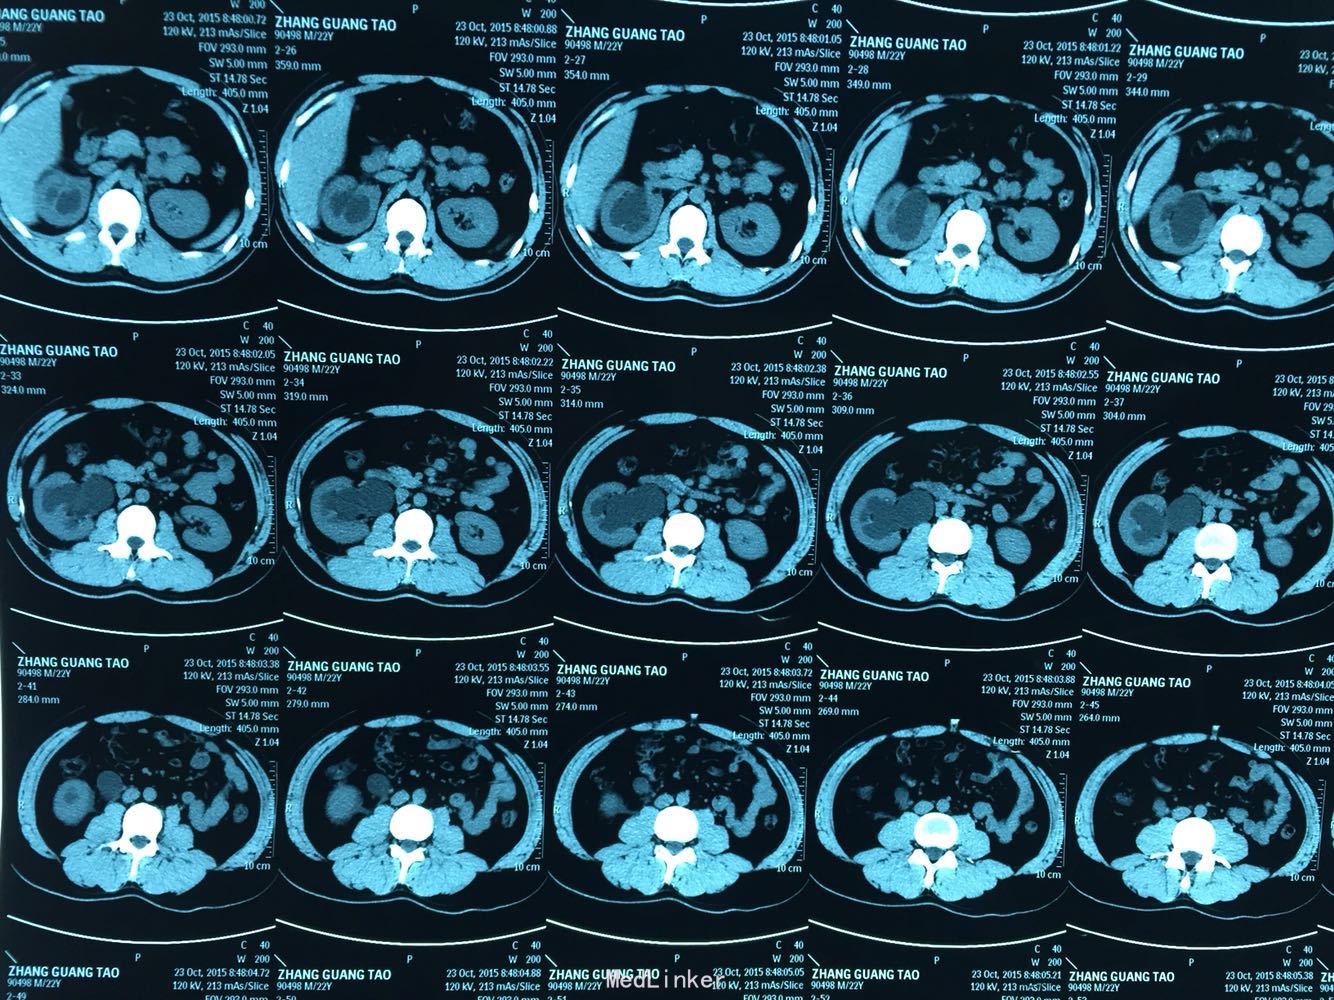

打开应用右肾积水,输尿管上段扩张,中下段未见显影。

辅助检查:泌尿系CTU:右肾积水,右输尿管上段扩张,右输尿管及肾周炎性渗出。

诊断:右肾积水,右输尿管上段扩张,右肾周及输尿管渗出?

该患者右上腹疼痛严重,伴腰痛,肾周及输尿管扩张,造影剂清晰显示,中下段未见确切输尿管影像。

疑点;肾周及输尿管有外渗,正常情况应有高热,本患者无发热,血象不高。

目前有两套方案:一是膀胱镜下逆行造影;二是介入下肾穿刺造瘘从上向下造影。